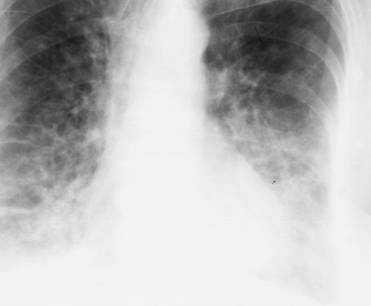

Fig. 30 – Staza pulmonara

Atunci cand rezistenta la fluxul sanguin dincolo de capilarele pulmonare creste, atunci presiunea in venele pulmonare va creste si ea determinand o hipertensiune venoasa sau postcapilara (≥ 15 mm Hg). Principalele semne radiologice ale tensiunii postcapilare sunt:

atunci cand presiunea capilara depaseste presiunea osmotica (25 mm Hg) are loc o transvazare in tesutul interstitial a fluidului ce contine fibrina si hematii; fluxul limfatic este crescut, si toate vasele limfatice fiind dilatate;

linii Kerley B, rezultate din ingrosarea septurilor interlobare;

linii Kerley A determinate de edemul perilimfatic;

diminuare difuza a transparentei pulmonare;

revarsat pleural;

atunci cand presiunea venoasa atinge valoare de 30 de mm Hg apare edemul intraalveolar: opacitate alveolara uni- sau bilaterala perihilara (edem pulmonar);

noduli hemosiderotici.